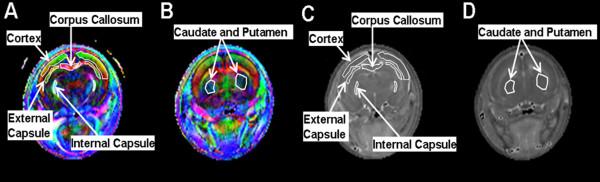

DTI data were acquired between postnatal day 7 (P7) and P12 in 12 rats with HCP induced at P2 and in 15 age-matched controls. Animals were euthanized at P11 or P22/P23 and brains were processed with immunohistochemistry for glial fibrillary acidic protein (GFAP), ionized calcium-binding adaptor molecule (Iba-1), and luxol fast blue (LFB) to assess astrocytosis, microglial reactivity and degree of myelination, respectively.

Hydrocephalic rats were consistently found to have an abnormally low (at corrected p-level of <0.05) fractional anisotropy (FA) value and an abnormally high mean diffusivity (MD) value in the cerebral cortex (CX), the corpus callosum (CC), and the internal capsule (IC). Immunohistochemical analysis demonstrated trends of increasing astrocyte and microglial reactivity in HCP rats at P11 that reached statistical significance at P22/P23. A trend toward reduced myelination in the HCP rats was also found at P22/P23. Correlation analysis at P11 for the CC demonstrated statistically significant correlations (or trends) between the DTI measurement (the decreased FA and increased MD values) and the GFAP or Iba-1 rankings. The immunohistochemical rankings in the IC at P22/P23 were also significantly correlated or demonstrated a trend with both FA and MD values.